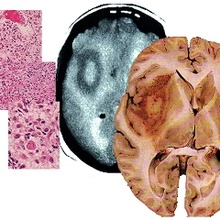

Новый метод борьбы с глиобластомой

Разные раковые клетки по-разному «защищаются» от лекарственных препаратов, мешая лечению. Как ученые реша...